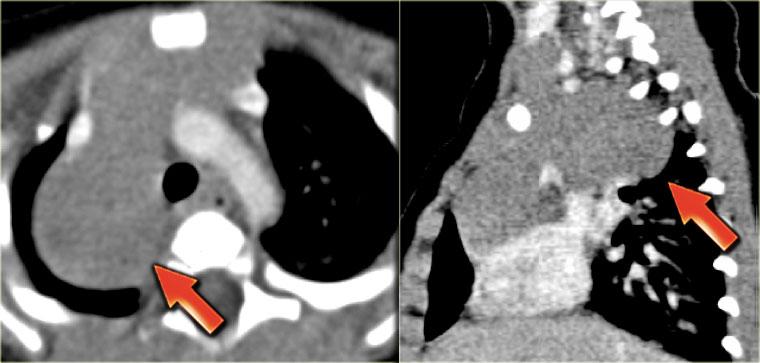

Phim ngực cho thấy các đặc điểm điển hình của u lympho Hodgkin, ví dụ: một khối trung thất trước.

Các hình ảnh CT của cùng bệnh nhân cho thấy một khối mô mềm lớn ở trung thất trước, xuất phát từ tuyến ức.

Có hạch cạnh khí quản kèm theo (mũi tên).

Hai trường hợp u lympho Hodgkin khác.

Các trường hợp này cũng cho thấy khối trung thất trước và hạch cạnh khí quản to.